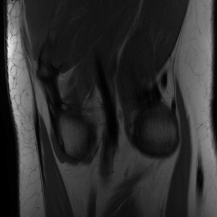

| Ground Truth | Initial | Global | LONDN-MRI | LONDN-MRI | Oracle |

| (1 iteration) | (2 iterations) | ||||

![]() |

| PSNR = dB | PSNR = 19.41 dB | PSNR = 26.52 dB | PSNR = 27.76 dB | PSNR = 27.85 dB | PSNR = 27.92 dB |